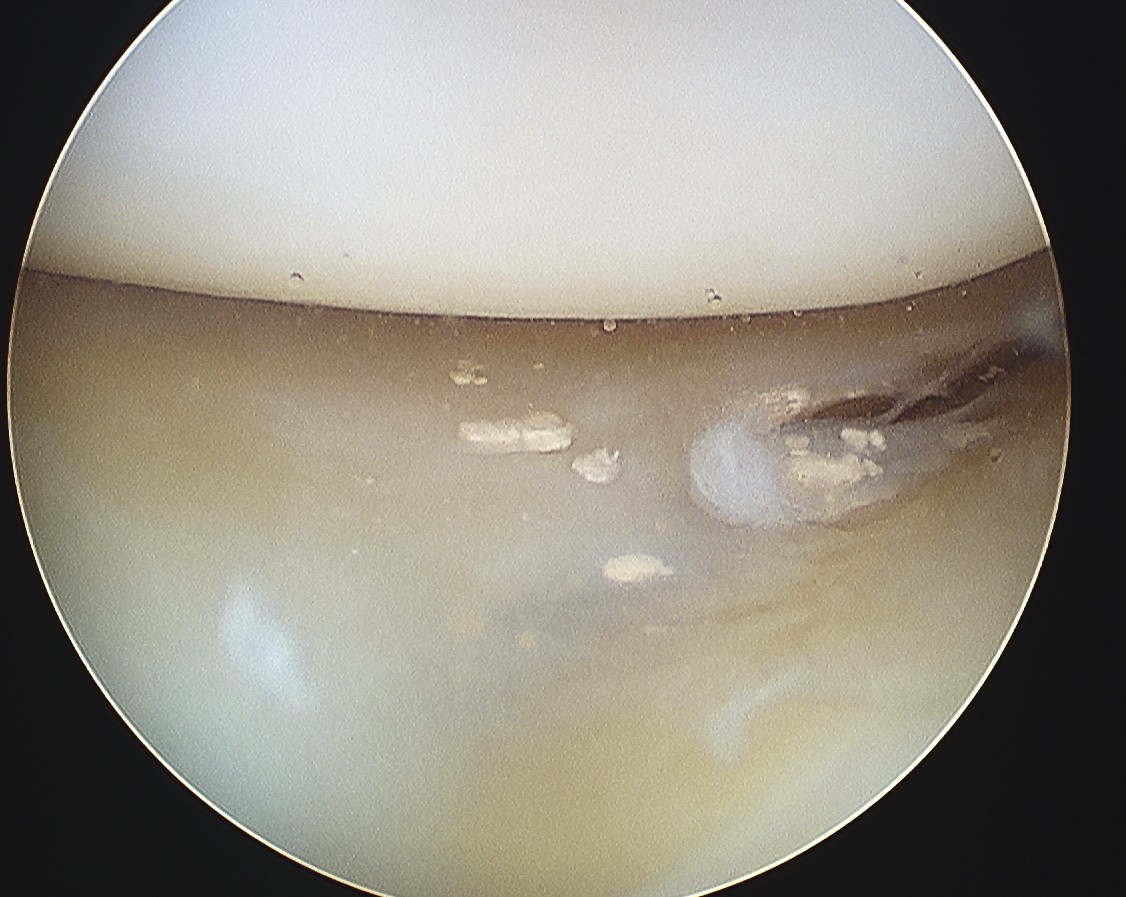

- chondrocalcinosis

- CPPD deposition in cartilage